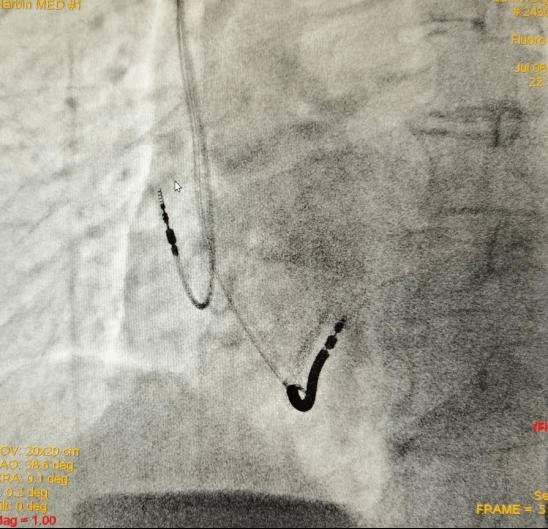

7月6日,东三省首例目前功能最全的3.0T磁共振(MRI)兼容植入式心律转复除颤器(ICD)在哈尔滨医科大学附属第一医院副院长李悦教授的支持下,在心内科七病房主任梁兆光教授、副主任谢荣盛教授团队努力下顺利完成。

梁兆光教授及谢荣盛教授结合病人特点,经过审慎讨论考虑建议她植入心律转复除颤器(ICD),从而有效预防猝死的发生。梁兆光教授考虑到患者预期寿命较长,未来接受MRI检查、诊断的需求较高,建议病人选择3.0T MRI全身兼容ICD。

谢荣盛教授表示,为患者植入的这款ICD属于目前功能最全面的3.0T MRI兼容ICD。它具有流线外形、长寿命、智能电击、房颤干预四大功能。这几项功能带给患者的优点是可以减轻囊袋的张力,使这个小刀口更容易长好,减少感染的发生;最大限度实现电击除颤的智能化,减少不恰当的除颤电击;预估使用年限长达10年,能够减少更换的次数,从而降低感染风险,也减少了患者的医疗费用和手术痛苦;通过独有的功能设计,可以减少房颤的发作时间和频率。